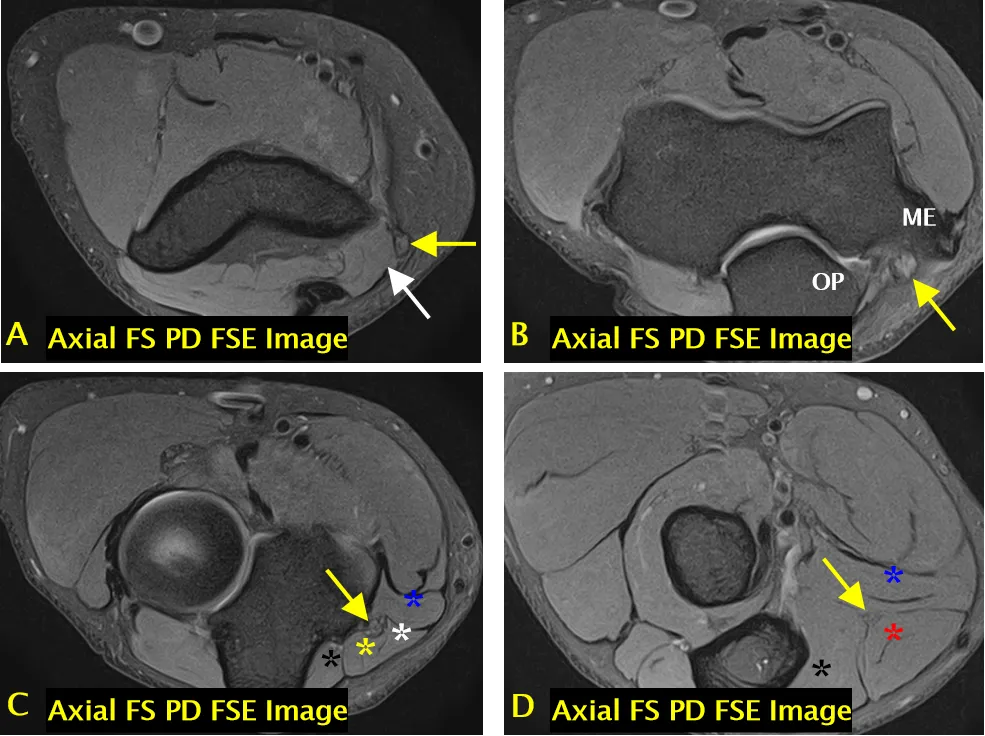

尺神经(黄色箭头标注);可见肱三头肌(长头)(A 中白色箭头标注)、指深屈肌(C 中黑色标注)、尺侧腕屈肌(肱骨头)(C 中白色标注)、尺侧腕屈肌(尺骨头)(C 中黄色标注)、尺侧腕屈肌(D 中红色标注)、指浅屈肌(C、D 中蓝色 * 标注);ME = 内上髁,OP = 鹰嘴

尺神经沟(骨纤维通道)结构

• 尺神经沟的底部由内侧副韧带后束和关节囊构成。

• 尺神经沟的顶部由尺神经沟支持带和尺侧腕屈肌筋膜深层(弓状韧带)构成。

内侧副韧带后束(蓝色箭头标注)、尺神经沟支持带(A 中箭头头标注)、弓状韧带(B 中箭头头标注)、尺神经(黄色箭头标注);可见尺侧腕屈肌(B 中黑色箭头标注)和共同屈肌肌腱(B 中白色箭头标注)。